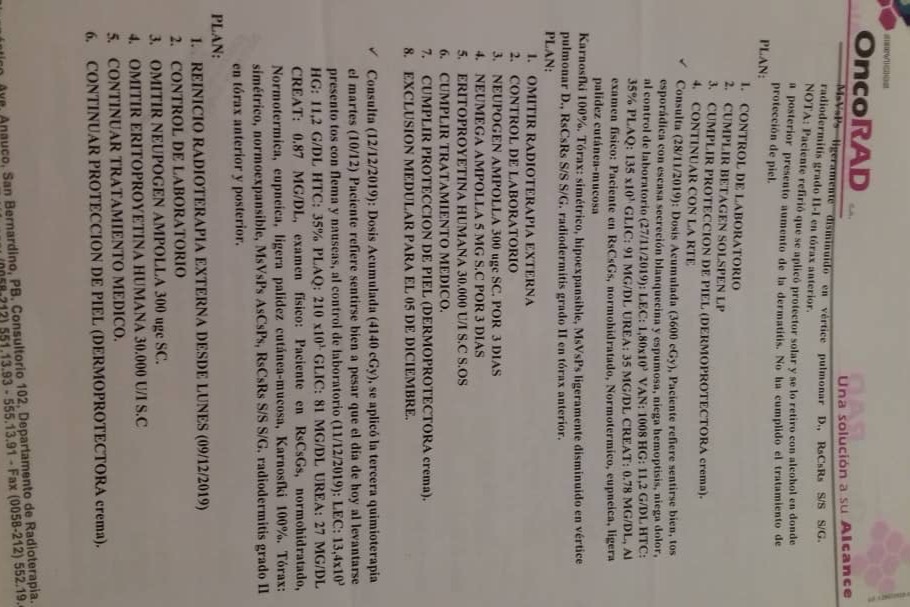

En septiembre de 2019 fue diagnosticada con cáncer de pulmón con una Lesión Ocupante de Espacio (LOE) de 2,5 cm y otra lesión en el Mediastino de 5,4 x 4,7 cm.

A través de varios familiares hemos logrado conseguir dinero para realizarle 36 ciclos de radioterapia y 6 de quimioterapia, además del tratamiento y todos los medicamentos requeridos hasta ahora, logrando una reducción importante del tamaño del tumor en pulmón en 40 %. Gracias a Dios la lesión en el mediastino se redujo también en un 80%.

A continuación les dejo el diagnóstico, los exámenes, y los presupuestos de los próximos exámenes que hay que hacerle a mi mamá.

In September 2019, she was diagnosed with lung cancer with a Space Occupying Injury (LOE) of 2.5 cm and another lesion in the Mediastinum of 5.4 x 4.7 cm.

Through several family members we have managed to raise money to perform 36 cycles of radiotherapy and 6 of chemotherapy, in addition to the treatment and all the medications required so far, achieving a significant reduction in the size of the tumor in the lung by 40%. Thank God the injury to the mediastinum was also reduced by 80%.

Down here I leave the diagnosis, exams, and budgets for the next exams to be done to my mom.